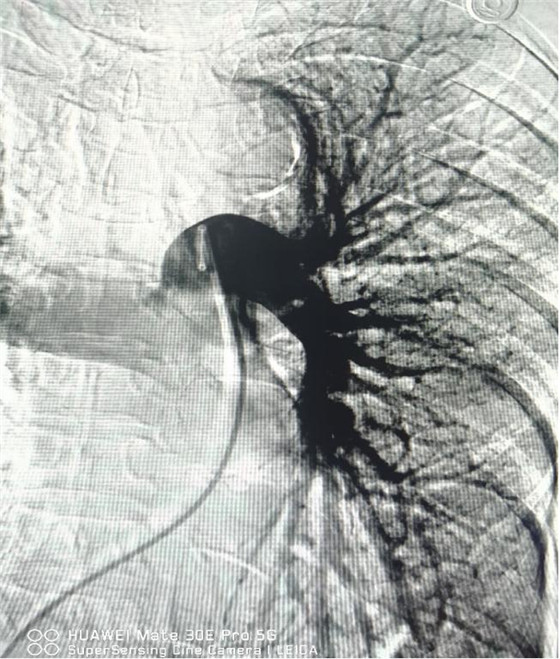

術(shù)后肺動脈血流恢復(fù)通暢

經(jīng)綜合評估并與家屬充分溝通后,局麻下行肺動脈造影,提示左肺動脈主干及左肺下葉動脈閉塞,立即予以經(jīng)皮肺動脈栓塞導(dǎo)管介入碎栓溶栓術(shù)。在心內(nèi)科韋鋒主任、郭良玉主治醫(yī)師及成婷護(hù)師的默契配合下,爭分奪秒順利完成手術(shù)。術(shù)后即刻復(fù)查肺動脈造影示左肺動脈主干及左肺下葉動脈恢復(fù)血流,生命體征穩(wěn)定,指脈氧恢復(fù)至100%。經(jīng)過精心治療與護(hù)理,目前患者已康復(fù)出院。